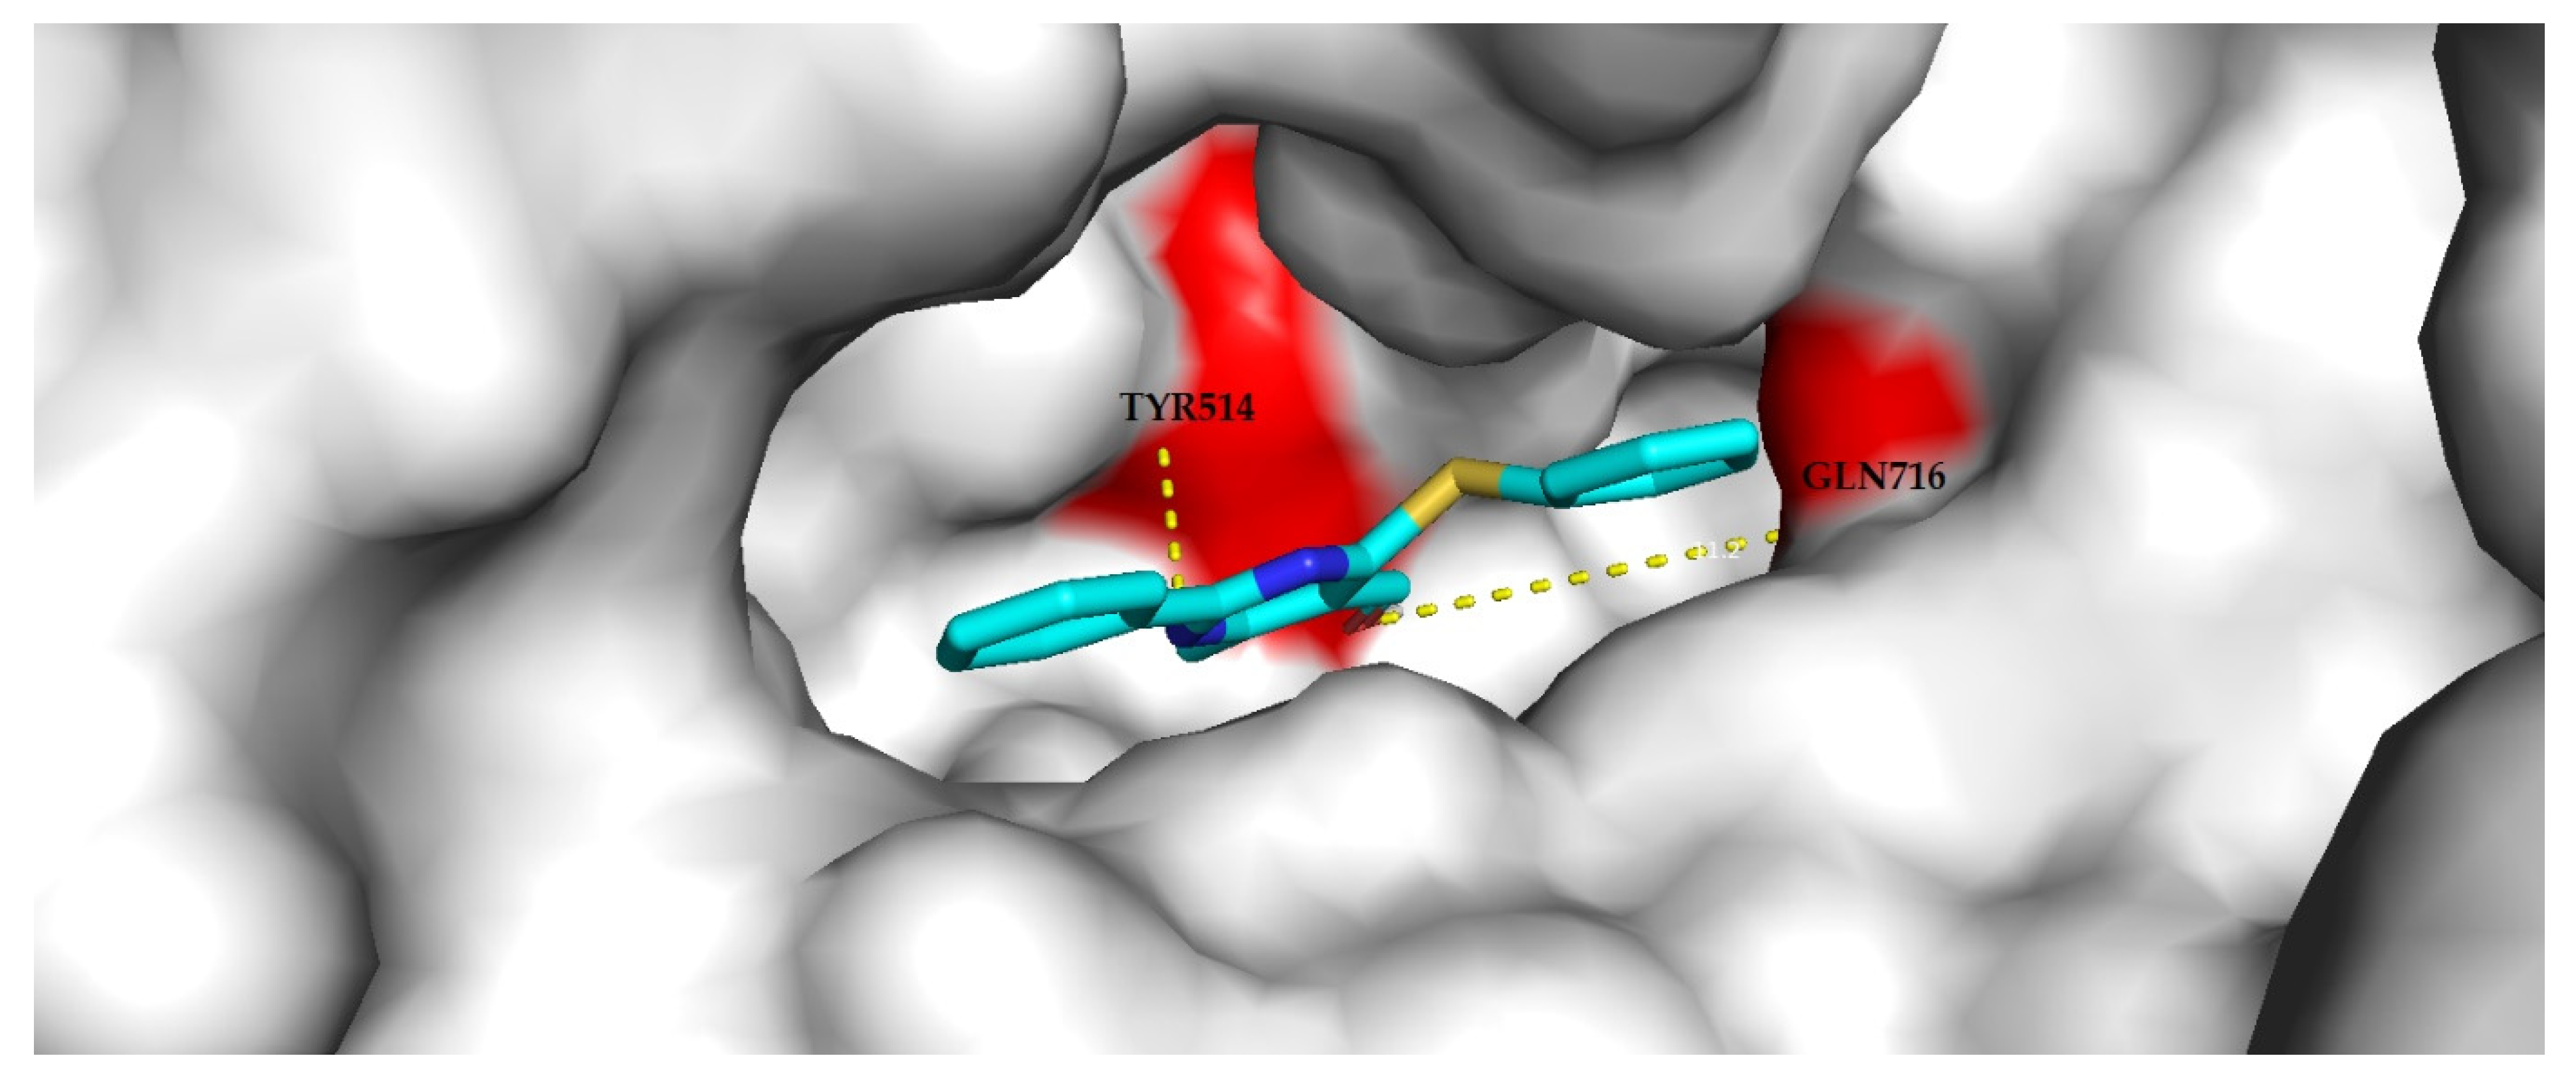

3.4.2. Molecular Docking Analysis

| Compound | Target Class | Target Name | Protein Data Bank (PDB) Accession Code |

|---|---|---|---|

| 3a | Phosphodiesterase | Phosphodiesterase 10A | 5B4L |

| Oxidoreductase | Cyclooxygenase-1 | 6Y3C | |

| 3g | Phosphodiesterase | Phosphodiesterase 4B | 1ROR |

| Family A G protein-coupled receptor | Adenosine A1 receptor | 5UEN | |

| 3h | Family A G protein-coupled receptor | Adenosine A1 receptor | 5UEN |

| Family A G protein-coupled receptor | Adenosine A2a receptor | 5IU4 |